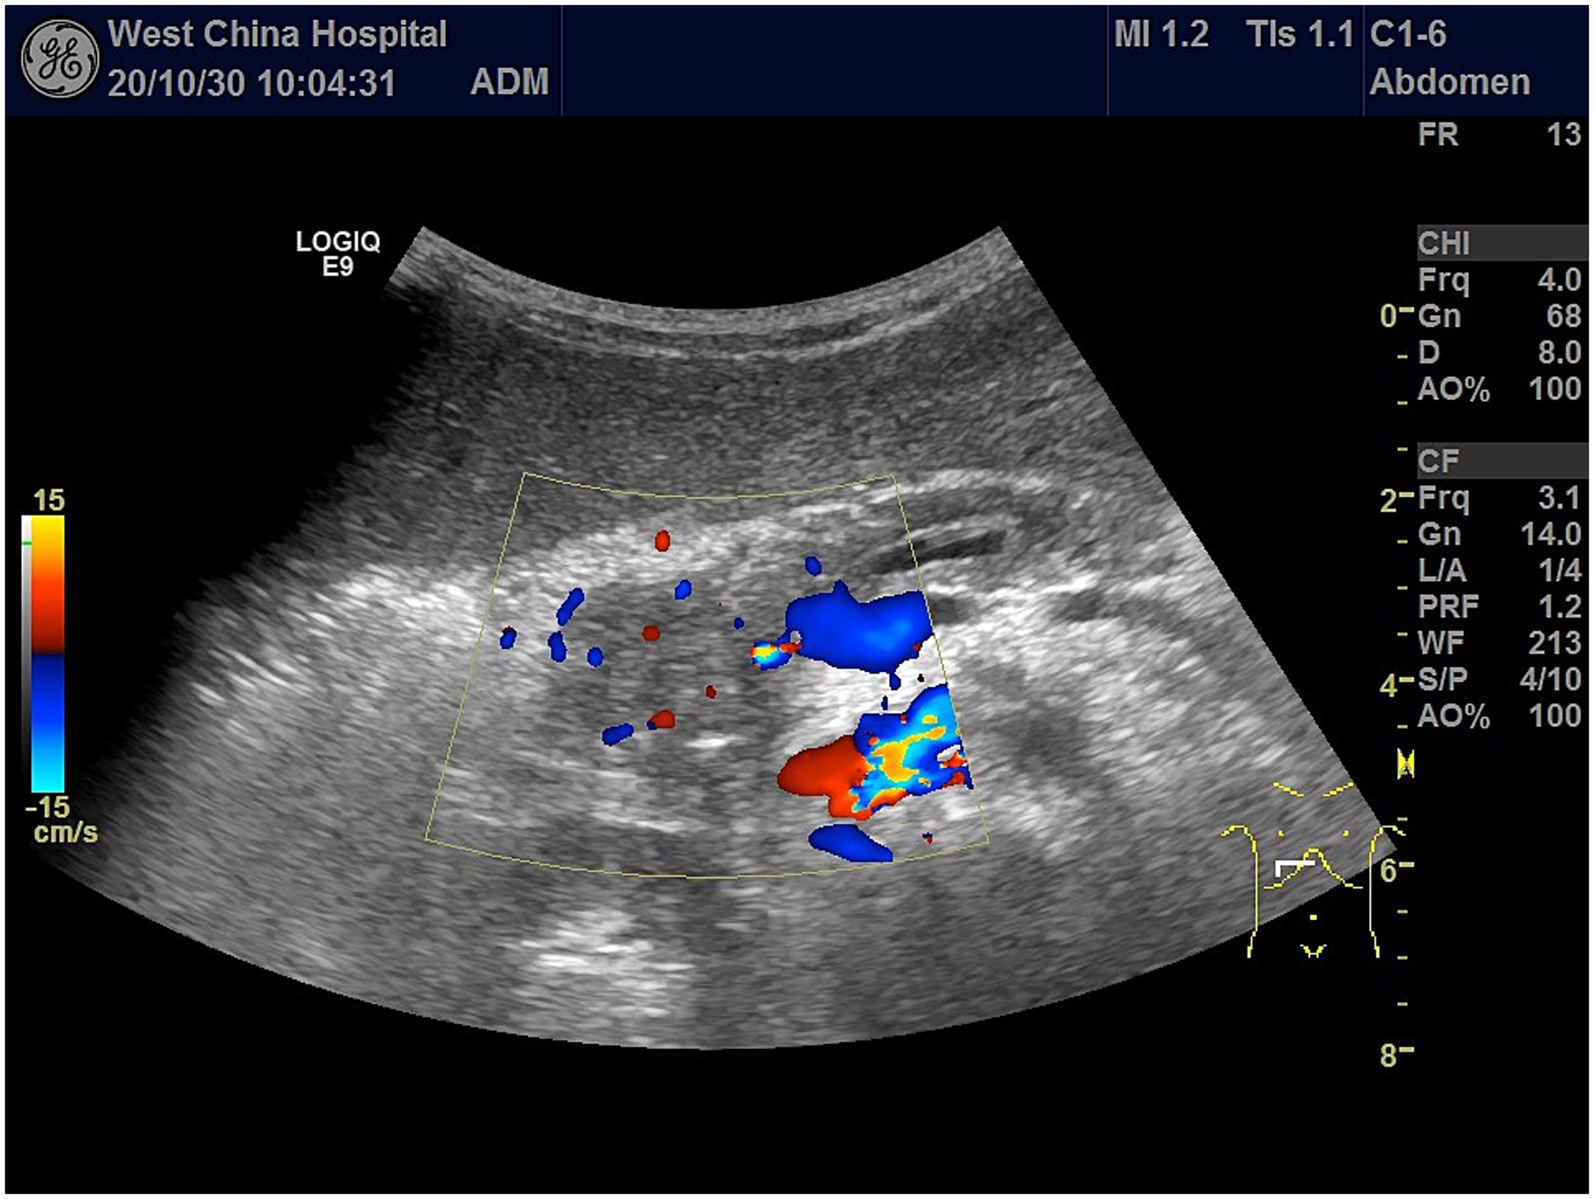

Ultrasound examination revealed a hypoechoic mass in the pancreatic head, measuring ~4.0 × 2.9 × 3.5 cm, with unclear borders and irregular morphology. Punctate blood flow signals (Adler blood flow grade 2) were observed within the lesions (Figure 3). Enhancement of the pancreatic parenchyma was observed 19 s after contrast injection. The lesion exhibited rapid, inhomogeneous hypoenhancement at 22 s after contrast administration and consistently maintained this inhomogeneous hypoenhancement. The imaging findings showed a hypoenhanced lesion in the arterial phase (Figure 4A) and lower enhancement in the portal venous phase (Figure 4B). By 80 s, the lesion began to washout, with nearly complete washout observed in the late phase (Figure 4C). This suggested the presence of a tumorigenic lesion. Gray-scale ultrasound revealed that the right side of the liver was significantly reduced in size compared to the left side of the liver. High-frequency ultrasound revealed findings consistent with liver cirrhosis, including an unsmooth liver envelope and heterogeneous parenchymal echogenicity; this was supported by a markedly elevated liver stiffness measurement of 26.1 kPa on shear wave elastography. The flow velocity in the portal venous system was markedly reduced. The gallbladder wall was thickened (0.5 cm), and the spleen was enlarged (13.4 × 3.4 cm). These ultrasound findings indicated that the patient may have cirrhosis and portal hypertension.

Figure 3

Color Doppler flow imaging of the pancreatic head showing an irregular hypoechoic mass with ill-defined margins, measuring approximately 4.0 × 2.9 × 3.5 cm, with punctate internal vascularity (Adler Grade 2).